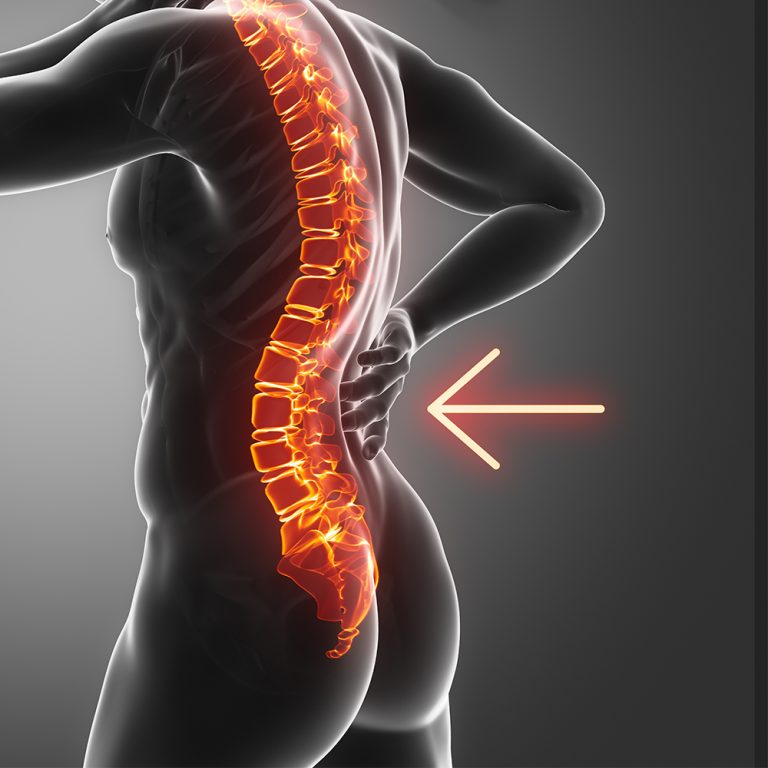

تمرینات ساده برای تقویت عضلات کمر

تمرینات ساده برای تقویت عضلات کمر درد و ضعف عضلات کمر یکی از شایعترین مشکلات امروزی است، بهویژه در افرادی که ساعتهای طولانی پشت میز

ارتباط کمردرد و استرس چیست؟ امروزه بسیاری از افراد بدون هیچگونه آسیب یا بیماری خاصی در ستون فقرات، دچار دردهای مزمن در ناحیه کمر میشوند.

چگونه هنگام کار در خانه از کمردرد جلوگیری کنیم

چگونه هنگام کار در خانه از کمردرد جلوگیری کنیم؟ نکاتی از دید متخصص طب فیزیکی و توانبخشی با افزایش کارهای آنلاین و دورکاری، بسیاری از

آیا صندلی محل کارتان به کمرتان آسیب میزند؟

آیا صندلی محل کارتان به کمرتان آسیب میزند؟ نکات ارگونومیک از دید متخصص طب فیزیکی و توانبخشی درد کمر یکی از شایعترین مشکلاتی است که

چه زمانی باید نگران کمردرد باشیم؟

چه زمانی باید نگران کمردرد باشیم؟ علایم هشدار دهنده کمردرد یکی از شایعترین مشکلات جسمی است و اغلب به دلایل غیر جدی مانند کشیدگی

چگونه کمردرد را در خانه تسکین دهیم

چگونه کمردرد را در خانه تسکین دهیم؟ تسکین کمردرد در خانه با روشهای ساده و خانگی امکانپذیر است، بهویژه اگر درد خفیف تا متوسط باشد

ده عادت روزمره که میتواند باعث کمردرد شود

ده عادت روزمره که میتواند باعث کمردرد شود کمردرد یکی از شایعترین مشکلات در جامعه امروزی است و بسیاری از افراد بدون آنکه بدانند، با